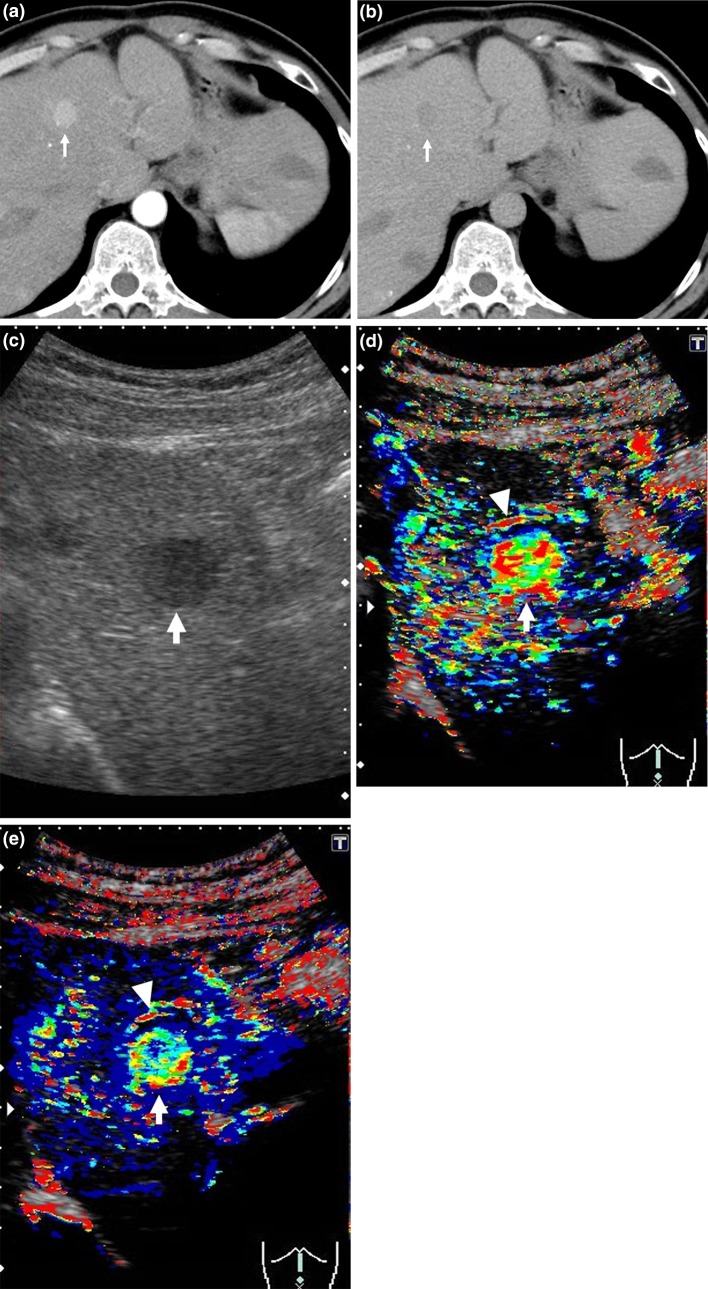

Fig. 2.

Clinical example of MT (+) group. The patient was a 50-year-old male with chronic hepatitis B virus. Sorafenib administration (400 mg/day) was started for advanced hepatocellular carcinoma (HCC). a Dynamic computed tomography (CT) scan in arterial phase before treatment showed a hypervascular lesion measuring 18 mm in diameter in S4 (arrow), which was the target lesion. b Dynamic CT scan in equilibrium phase before treatment showed a hypoattenuating lesion in S4 (arrow). c Gray-scale ultrasonography showed a low echoic tumor measuring 18 mm in diameter in S4 (arrow). This tumor was established as a target lesion. d The color mapping image before treatment showed primarily red, yellow, or green in the tumor (arrow). A large artery near this tumor was regarded as the reference point (arrow head). e The color mapping image 2 weeks after treatment showed primarily light blue or blue in the tumor (arrow). The same artery before treatment was regarded as the reference point (arrow head)